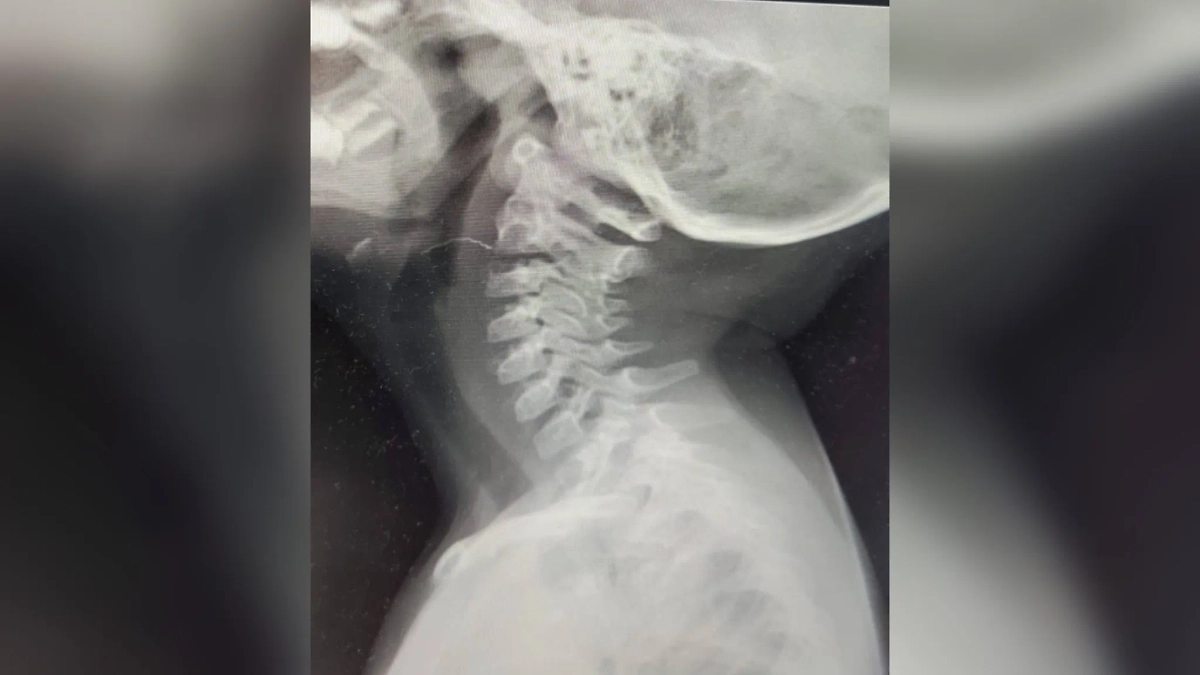

Врачи спасли девочку с проволокой в горле. Фото © Минздрав Московской области

"Мы обследовали ребёнка с помощью фиброскопа — специального эндоскопического прибора для осмотра труднодоступных зон — и увидели проволоку больше двух сантиметров, застрявшую в горле малышки. Мы удалили её при помощи микрохирургической и эндоскопической техники. Ребёнок был под седацией, и благодаря максимально нетравматичному способу хирургического вмешательства у девочки не осталось никаких внешних разрезов на теле", — описал ход операции глава отделения оториноларингологии МОНИКИ им. М.Ф. Владимирского Виктор Егоров.